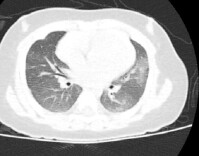

百万粉丝网红“干巴大叔”因癌去世,认识这种癌刻不容缓!